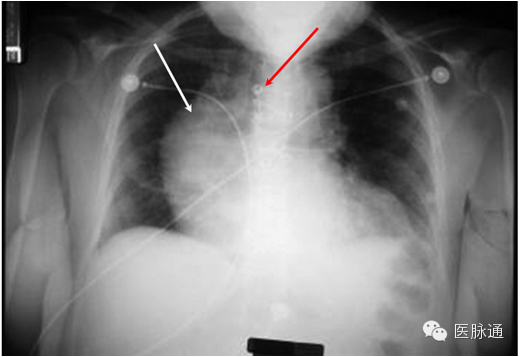

张力性气胸是指空气蓄积于胸膜腔内。当受损肺组织形成单向活瓣,造成空气只能进入而无法离开胸膜腔,即形成张力性气胸。应根据临床表现作出张力性气胸的诊断,包括气管向对侧移位,同侧叩诊过清音,同侧呼吸音降低,颈静脉充盈以及低灌注。典型的X线表现包括同侧肺塌陷(图3白色箭头)伴肋间隙增宽,以及纵隔向对侧移位(图3红色箭头)。若张力性气胸发生于左侧,则左侧膈肌下降,但若发生于右侧,则肝脏可限制膈肌的下降。

图3